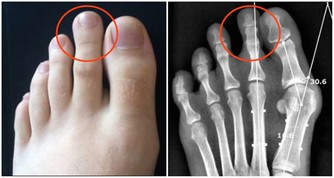

*****9.高膽固醇血症有時可能會表現在皮膚上。*****

有些血清總膽固醇高的人,會在眼皮、關節、雙手或身體其他部位長出黃中帶紅的腫塊(醫學上被稱為黃色瘤)。此外,糖尿病患者和患有家族性高膽固醇血症這種遺傳病的人也有可能長黃色瘤。醫生建議人們從20歲起每3年檢查一次,或者根據醫生的建議更為頻繁地檢查。